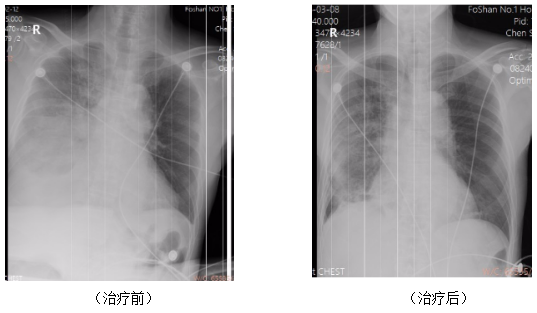

在整套规范、高效的综合救治下,患者病情迎来快速转机,肺部炎症得到有效控制,呼吸功能逐步恢复。入院8天后,患者成功拔除气管插管,脱离有创呼吸机支持,自主呼吸恢复平稳。后续医护团队继续根据患者病情调整抗感染及支持治疗方案,加强康复护理,患者肺炎症状持续好转,各项生命体征恢复正常,最终顺利康复出院。